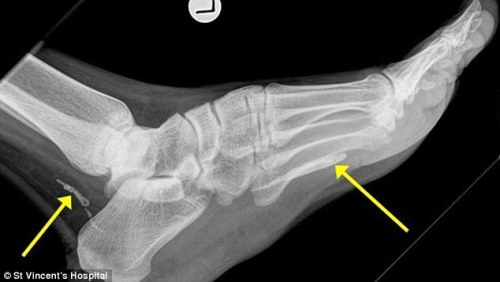

وأفادت صحيفة "سيدني مورننغ هيرالد" ان الرجل البالغ من العمر 38 سنة، شكا من ألم وتورم في قدمه فتوجه إلى مستشفى في سيدني حيث أجريت له صورة بالأشعة كشفت عن وجود دودة في قدمه.

وتأكد أن الدودة موجودة في قدمه منذ عدة سنوات، ذاك انها من النوع الذي يعيش في السودان وليست موجودة في أستراليا التي هاجر إليها قبل أكثر من 4 سنوات.